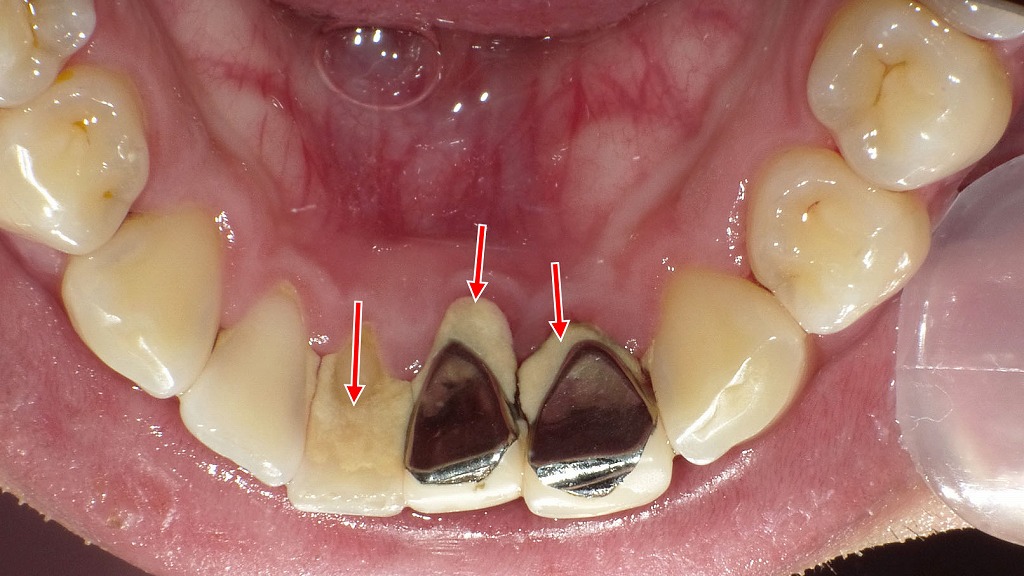

40代女性の歯周病症例

この写真は、40代女性の口腔内(前歯部)を示しています。上顎前歯の歯肉や下顎前歯の被せ物に、いくつかの臨床的特徴が確認されます。

🩺 主な臨床所見

■ 上顎前歯部(上の前歯)

- 歯肉退縮(しにくたいしゅく)

歯ぐきが下がり、歯根の一部が露出しています。特に中切歯・側切歯の間で顕著です。

➤ 長年の歯周病の進行や、ブラッシング圧過多、加齢変化が要因と考えられます。 - 歯肉の発赤と出血

歯肉縁に炎症が見られ、軽度の出血があります。

➤ 慢性歯周炎を示唆します。 - 補綴物(被せ物)の辺縁不適合

クラウンのマージン部(歯と被せ物の境目)に隙間や黒変が見られます。

➤ 二次カリエスやプラーク停滞の原因となる可能性があります。

■ 下顎前歯部(下の2番から2番:側切歯~中切歯)

- **保険の硬質レジン前装冠(こうしつレジンぜんそうかん)が装着されています。

表面にステイン(着色汚れ)**が沈着しており、黄褐色~茶褐色の変色が確認されます。

➤ コーヒー・タバコ・茶渋・経年的な劣化によるものです。

➤ レジン素材のため、長期使用で吸水や微細な亀裂により着色しやすい特徴があります。

🔬 総合評価

- 慢性歯周病による歯肉退縮・炎症・出血が進行しており、

補綴物周囲のプラークコントロール不良が認められます。 - 下顎前歯のレジン前装冠は経年劣化とステイン沈着が明らかで、審美的な低下もみられます。

💡 対応・治療の方向性

- 歯周基本治療(スケーリング・ルートプレーニング)

➤ 歯石とプラークを除去し、炎症を改善。 - ブラッシング指導と歯間清掃習慣の改善

➤ 歯肉退縮部や補綴物の境界を重点的に清掃。 - 補綴物の再評価・再製作の検討

➤ 適合不良や変色したクラウンをセラミックなど審美性の高い素材に交換。 - 定期的メンテナンス

➤ 3〜4ヶ月ごとの歯周メンテナンスで再発防止。